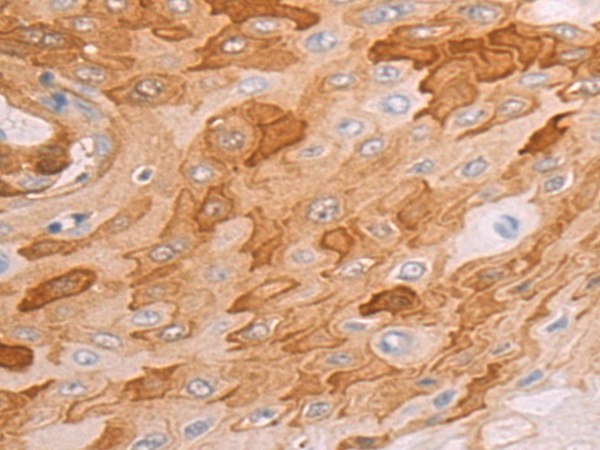

分类: 科研抗体货号: P11147别名: TYH; DYT14; DYT5b应用: IHC反应种属: Human